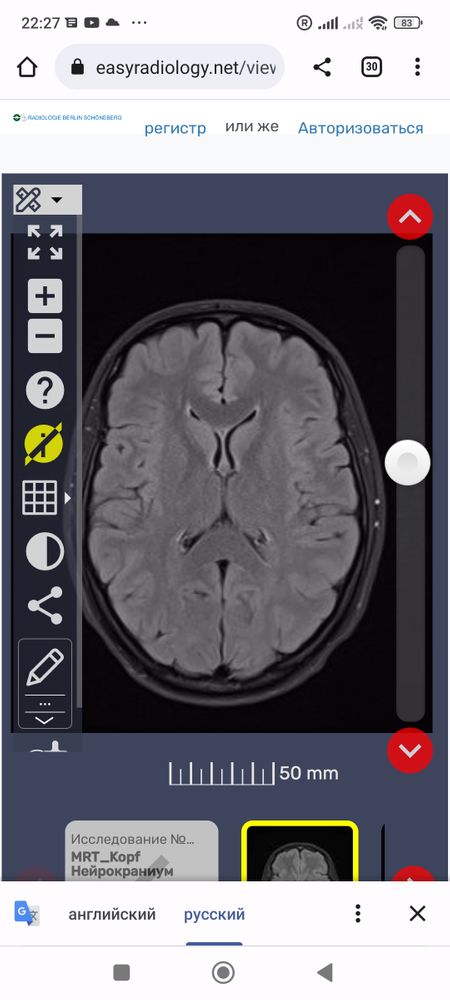

Что это за белые точки вокруг мозга? И все ли впорядке